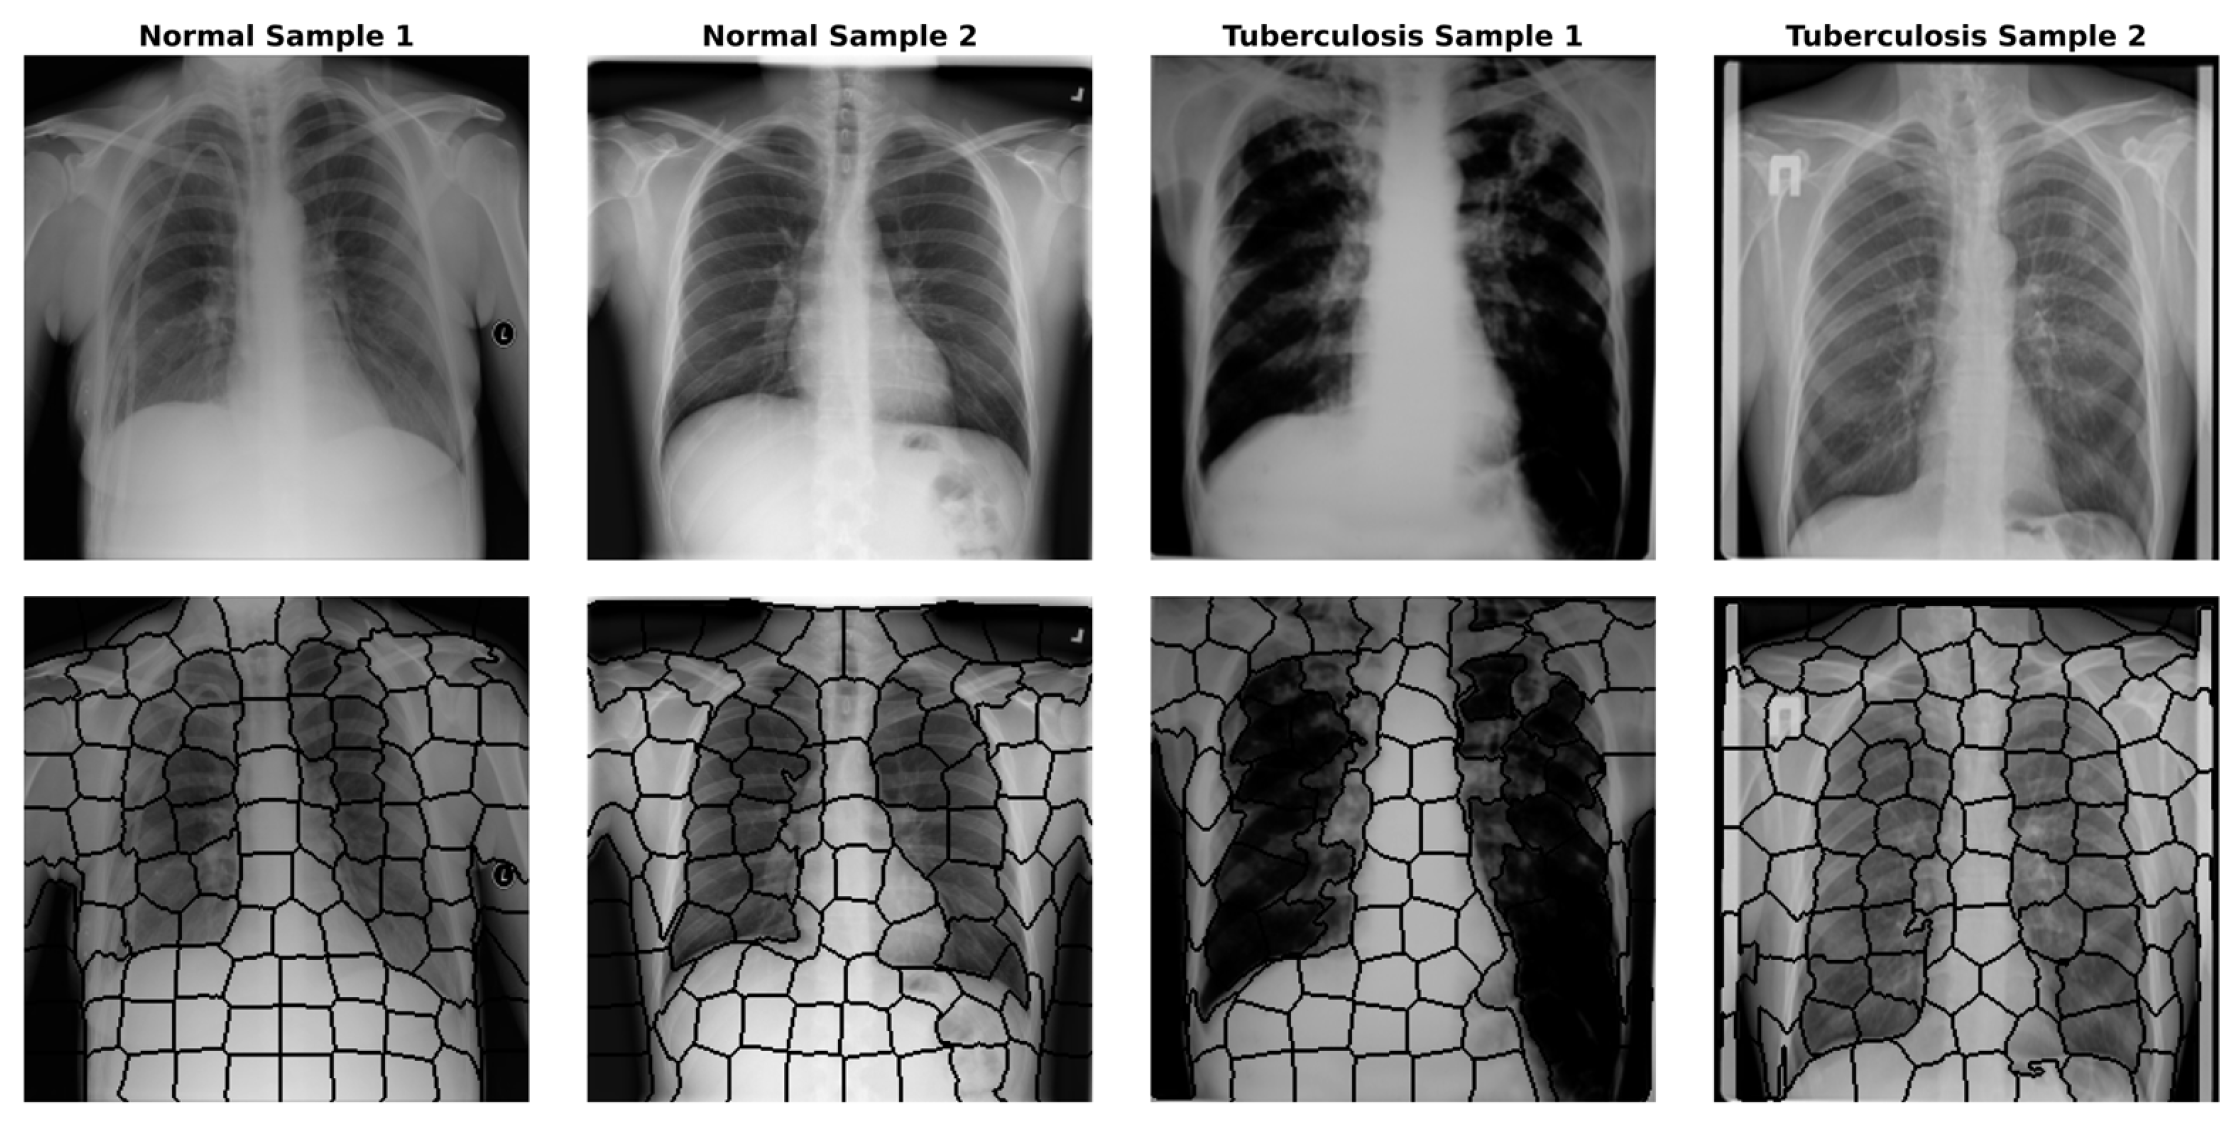

4.2. Image to Graph

- Colour and Intensity: Instead of the RGB space, we utilised the CIELAB colour space, which is perceptually uniform. We calculated the mean values of the L, A, and B channels for pixels within to represent average intensity and colour variations, which are crucial for identifying lesions under varying illumination conditions.

- Texture Descriptors: Since tuberculosis significantly alters lung tissue texture (e.g., infiltrations or consolidation), we extracted texture features to capture these irregularities. We computed Local Binary Patterns (LBP) histograms (radius = 3, points = 24) to encode micro-texture invariance. Additionally, Haralick features (Contrast, Correlation, Energy, and Homogeneity) were derived from the Grey-Level Co-occurrence Matrix (GLCM) to quantify structural dependencies at the regional level.

- Shape Invariants: To characterise the geometry of segmented regions independent of their orientation or scale, we calculated the seven invariant Hu Moments for each superpixel mask. This helps the model distinguish specific anatomical shapes regardless of patient positioning.

- Spatial Location: The normalised centroid coordinates (x,y) were included to allow the GNN to learn position-dependent priors, such as the likelihood of infection in specific lung lobes.